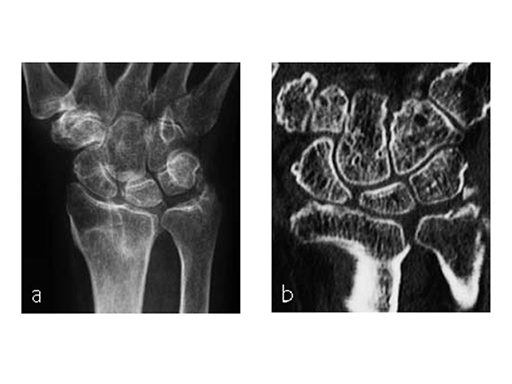

Case 2: Painful ulno-carpal abutment

A 32-year-old man suffered torsional trauma about the right wrist, with TCFF rupture. A failed arthroscopic repair had taken place. Constitutional ulna plus. Symptoms included pain and impaired function about the wrist and forearm. Painful DRUJ (DASH: 22, PWRE: 21).

The amount of correction required was 2.5 mm. The preoperative x-ray showed positive ulna variance.